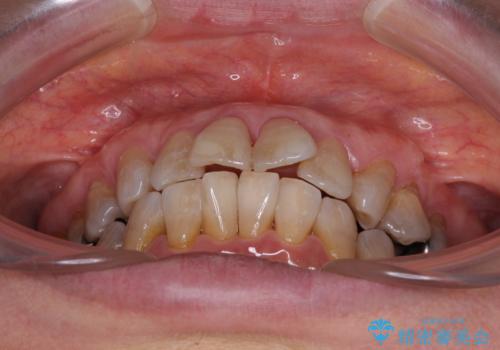

- 突出した口元を引っ込めることを希望して来院された患者様です。

上下左右第一小臼歯4本を抜歯して、口元を改善するワイヤー矯正を行うこととしました。

長年気にされていた口元の突出感が改善されたため、もっと若い時分に矯正をすればよかったと思われていました。